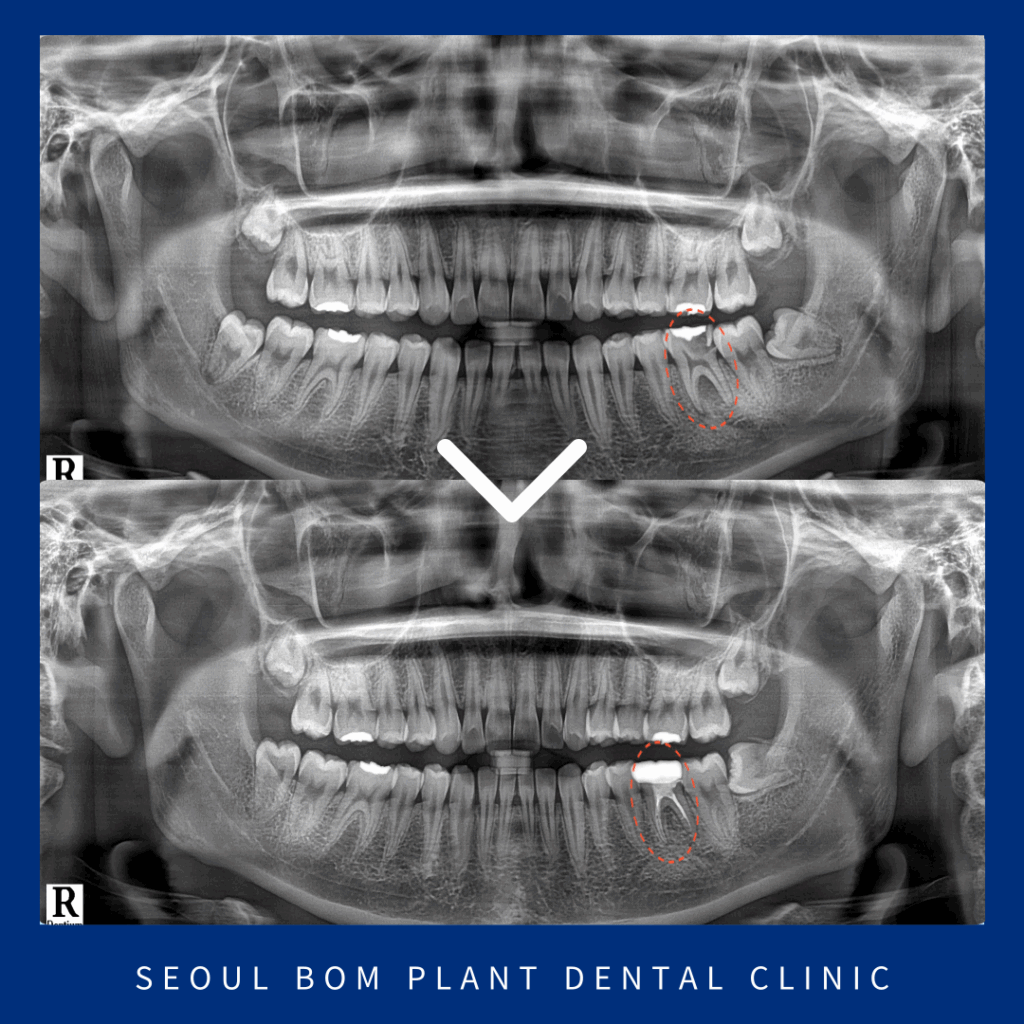

촬영 날짜 : 2022.11.30

아래턱 왼쪽 첫 번째 큰 어금니(#36)의

치근 분기부에서

까맣게 심한 골소실이 보였습니다.

촬영 날짜 : 2025.03.25

2년이 경과한 뒤의

x-ray 사진인데요.

처음 내원 당시와

비교해 보면 골재생이 많이 되어

안정적인 예후를 확인할 수 있었습니다.